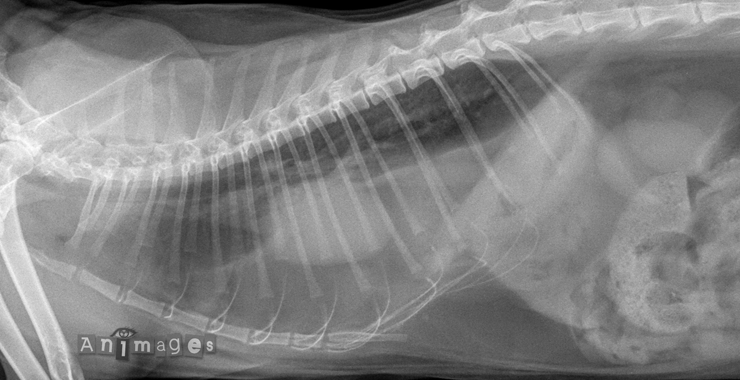

Latérale